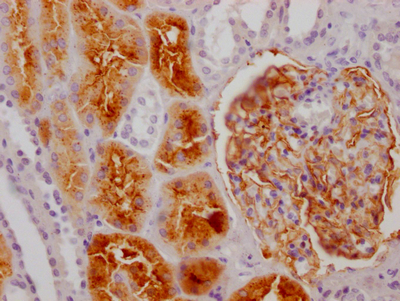

ApplicationELISA, IHC; Recommended dilution: IHC:1:50-1:200